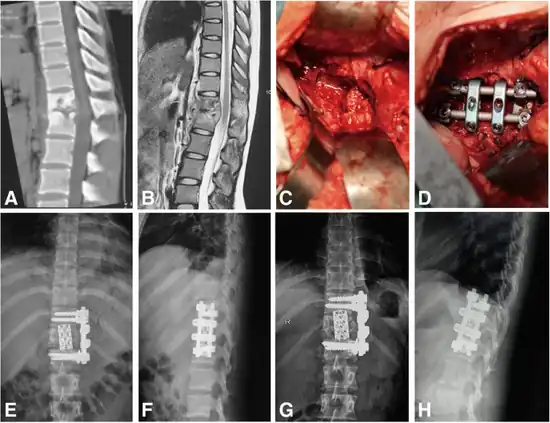

Surgical intervention is required for patients with Pott's disease in the event that there is a need for tissue sampling to clarify diagnoses, resistance to chemotherapy, neurologic deficits , paravertebral abscesses formed from bacterial induced immune response, and kyphotic deformities leading to instability of the spine.[1] However, surgery is up to shared clinical decision making and not an intervention that is defaulted to, as guidelines tend to lead towards less invasive procedures such as chemotherapy and anti-tuberculosis medications.[26]

Typical surgical techniques used are as follows:

- Posterior decompression and fusion with bone autografts[1][27]

- Anterior debridement/decompression and fusion with bone autografts[1][27]

- Anterior debridement/decompression and fusion followed by simultaneous or sequential posterior fusion with instrumentation[1][27]

- Posterior fusion with instrumentation followed by simultaneous or sequential anterior debridement/decompression and fusion[1][27]

Anterior debridement/decompression and fusion

The goal of the anterior debridement/decompression and fusion with bone autografts procedure is to relieve pressure on the spinal cord and nerves along the anterior side of the spinal cord and help prevent the progression of kyphosis in active disease.[29][30]

The anterior approach is often recommended instead of the posterior approach in cases where only single segments of the vertebrae are affected, and in the event that there is no destruction or collapse of the posterior elements.[30]

In anterior debridement and decompression, tissue damaged by the onset of disease is removed along with vertebral elements and intervertebral discs that are impinging on the spinal cord and/or nerves in the spine.[30]

Vertebrae can then be fused together through the use of grafts or instrumentation to provide more structural support for the spine and back.[30]